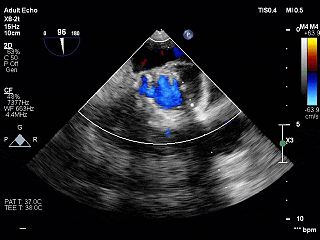

TEE长轴:瓣膜深度可

TEE短轴:瓣膜展开良好,仅少量瓣周漏

-

主瓣峰值流速由术前4.2m/s降至术后1.69m/s

主瓣峰值压差由术前70mmHg降至术后11mmHg